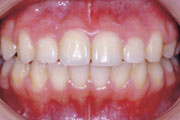

症例3:開咬(オープンバイト)